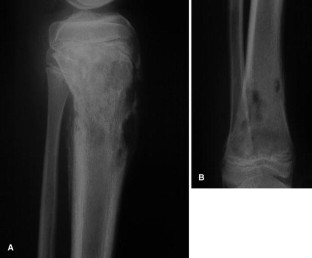

The SAPHO syndrome was a term coined to include a variety of musculoskeletal disorders associated with skin conditions, mainly palmoplantar pustulosis and acne conglobata. It is more correctly a spectrum which includes the following: skin lesions, osteoarticular manifestations of synovitis hyperostosis and osteitis affecting particular target sites, and·a clinical course marked by relapses and remissions. The major sites of involvement are the anterior chest wall, the spine, long bones, flat bones, and large and small joints. The distribution and severity of involvement varies from the adult to the pediatric form of chronic recurrent multifocal osteomyelitis (CRMO). The diagnosis of SAPHO syndrome is not difficult when the typical osteoarticular lesions are located in characteristic target sites. The diagnosis is more difficult if atypical sites are involved and there is no skin disease.